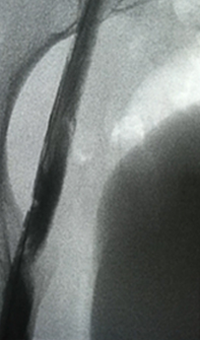

Pharmacomechanical revascularization of extensive iliofemoral thrombus

60 year old female presented with 4 weeks calf pain 1 week swelling.

Procedural steps

• Power Pulse delivery 10mg tPA

• 20 minute dwell time

• ZelanteDVT runtime 415 seconds

• Total case time 90 minutes

Xray of Iliofemoral thrombus pre-treatment and Power Pulse™ delivery

Iliofemoral thrombus pre-treatment (left) and Power Pulse delivery (right)

Xray of veins post-ZelanteDVT mechanical thrombectomy.

Post-ZelanteDVT  Mechanical Thrombectomy

Xray of veins post-ZelanteDVT runtime 415 seconds.

Post-ZelanteDVT runtime 415 seconds

Images Courtesy of Charles Wyble M.D. – Vascular Surgical Associates, Marietta, Georgia – January 5, 2016